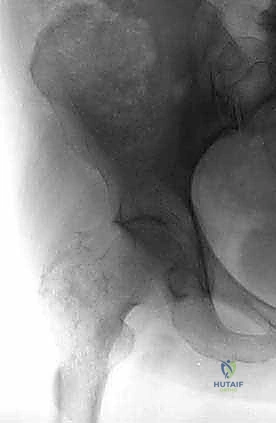

- الأشعة السينية العادية (X-rays): هي الخطوة الأولى دائماً. تظهر النقائل الحالة للعظم كبقع داكنة (ثقوب) في العظم، بينما تظهر النقائل البانية كبقع بيضاء كثيفة. الأشعة السينية ضرورية لتقييم خطر الكسر.

* النقائل الحالة للعظم (Osteolytic): (مثل سرطان الثدي والرئة والكلى) تؤدي إلى تدمير مفرط للعظم، مما يتركه مليئاً بالفجوات وهشاً للغاية وقابلاً للكسر بسهولة.

* النقائل البانية للعظم (Osteoblastic): (خاصة في سرطان البروستاتا) تؤدي إلى تكوين عظم جديد ولكنه عظم عشوائي وضعيف البنية، وهو أيضاً عرضة للكسر.

* النقائل المختلطة: تحتوي على كلا النوعين من التدمير والبناء.

3. الجزء السفلي من عظم الفخذ (Distal Femur)

هذا الجزء يتسع ليشكل اللقمتين الفخذيتين (Condyles) اللتين تتمفصلان مع عظم الظنبوب (القصبة) لتكوين مفصل الركبة. النقائل في هذه المنطقة تؤثر بشكل مباشر على ميكانيكا الركبة وتسبب آلاماً شديدة عند ثني أو فرد الساق. الجراحة هنا تتطلب دقة متناهية للحفاظ على أربطة الركبة (الصليبية والجانبية) أو استبدال المفصل بالكامل بمفصل صناعي للأورام إذا كان التدمير العظمي واسعاً.